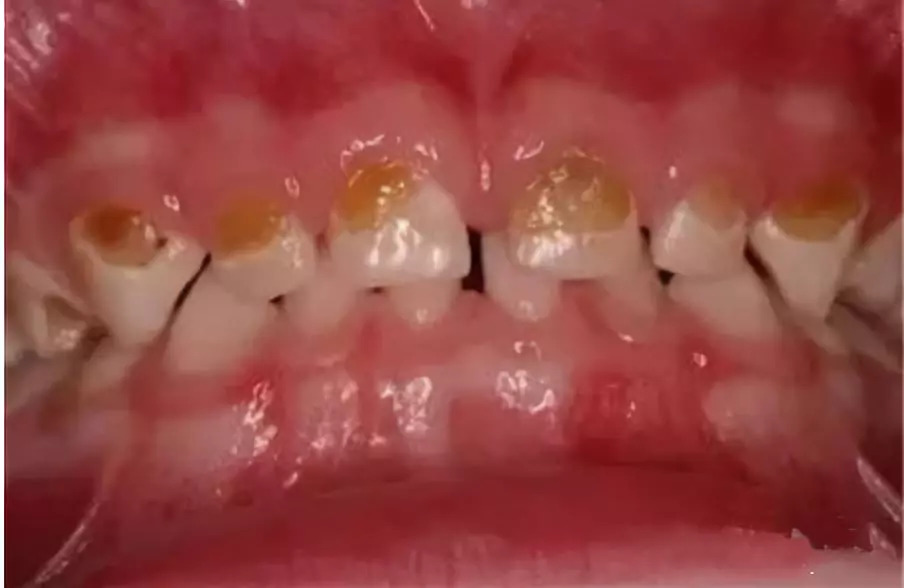

1. 牙齿●患龋↓↓

蛀牙在医学上称之为龋齿,是由于食物在牙齿表面存留,驻扎在牙齿上的细菌会分解这些食物而产生酸,这些酸会腐蚀牙齿,使其脱矿,继而软化腐烂,最终牙体崩解形成龋洞。若蛀牙不及时治疗,任其发展,龋洞会越来越大,还会侵及这颗牙齿的神经血管所在的牙髓腔,导致整个牙体崩解,引发牙髓发炎、牙根尖发炎,出现牙痛或长脓包的现象。